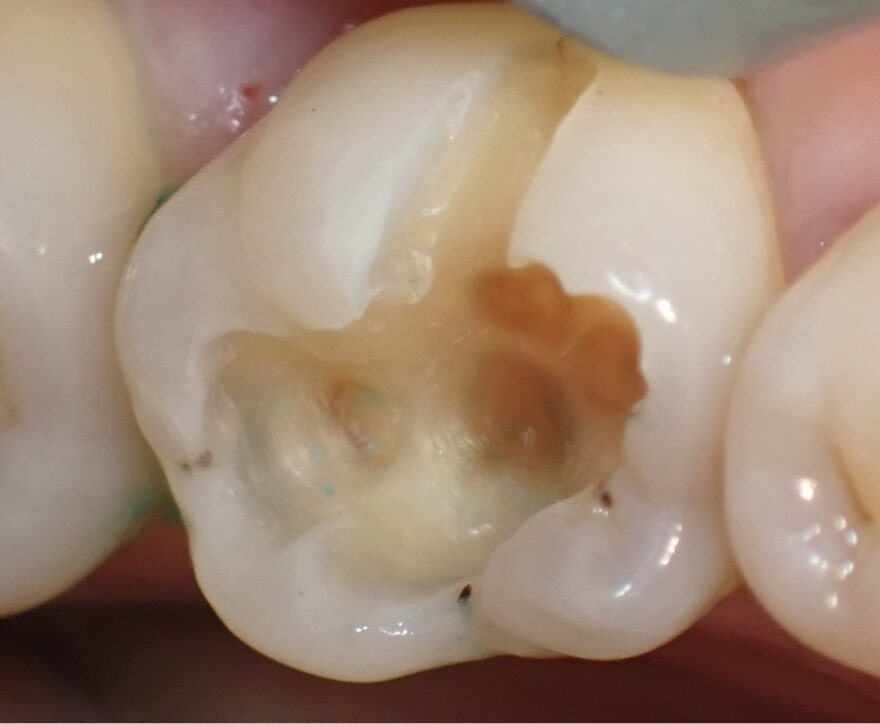

銀歯内部の虫歯をセラミックで修復した治療例

治療前後の経過写真

症状が全くなくても、銀歯を入れてから5年以上経過していると、深部でむし歯が再発していることがほとんどです。

銀歯は劣化が早く、隙間から細菌が侵入することが、むし歯再発の原因です。

茶色くても硬い箇所は温存しておいても問題ありません。

噛み合わせに関与している部分が失われてしまったため、セラミッククラウンを被せる必要があります。

保険適応のレジン充填(光硬化型のプラスチック)を詰めても、強度に劣るため、咬合力に耐えれず、染みてしまい、しっかり噛むことができません。